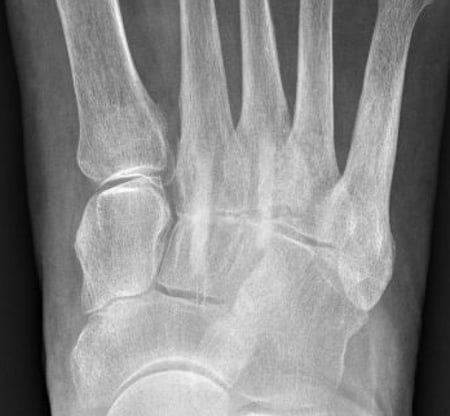

Röntgenbild postoperativ

Versorgung der Arthrose mit Shark Screw® Transplantaten 5,0mm.